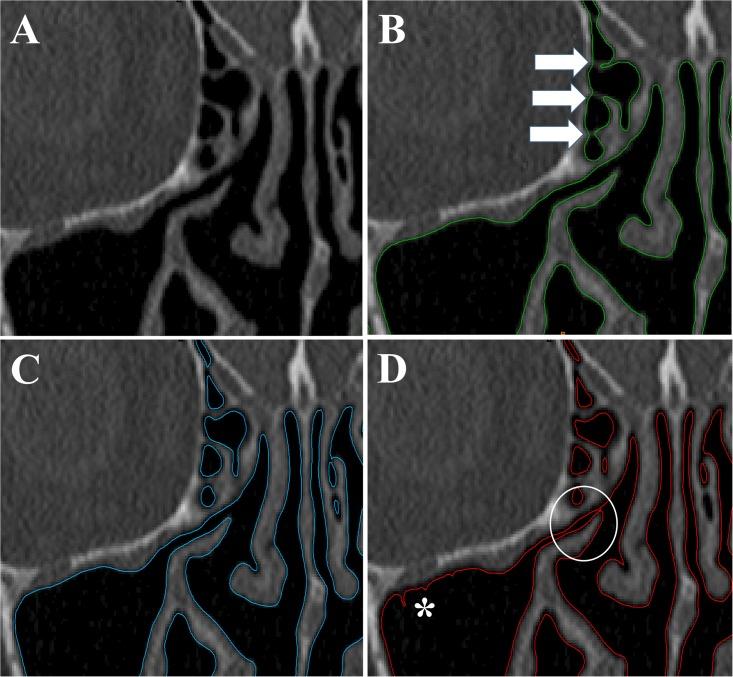

Computational fluid dynamics (CFD) allows quantitative assessment of transport phenomena in the human nasal cavity, including heat exchange, moisture transport, odorant uptake in the olfactory cleft, and regional delivery of pharmaceutical aerosols. The first step when applying CFD to investigate nasal airflow is to create a 3-dimensional reconstruction of the nasal anatomy from computed tomography (CT) scans or magnetic resonance images (MRI). However, a method to identify the exact location of the air-tissue boundary from CT scans or MRI is currently lacking. This introduces some uncertainty in the nasal cavity geometry. The radiodensity threshold for segmentation of the nasal airways has received little attention in the CFD literature. The goal of this study is to quantify how uncertainty in the segmentation threshold impacts CFD simulations of transport phenomena in the human nasal cavity. Three patients with nasal airway obstruction were included in the analysis. Pre-surgery CT scans were obtained after mucosal decongestion with oxymetazoline. For each patient, the nasal anatomy was reconstructed using three different thresholds in Hounsfield units (-800HU, -550HU, and -300HU). Our results demonstrate that some CFD variables (pressure drop, flowrate, airflow resistance) and anatomic variables (airspace cross-sectional area and volume) are strongly dependent on the segmentation threshold, while other CFD variables (intranasal flow distribution, surface area) are less sensitive to the segmentation threshold. These findings suggest that identification of an optimal threshold for segmentation of the nasal airway from CT scans will be important for good agreement between in vivo measurements and patient-specific CFD simulations of transport phenomena in the nasal cavity, particularly for processes sensitive to the transnasal pressure drop. We recommend that future CFD studies should always report the segmentation threshold used to reconstruct the nasal anatomy.

计算流体动力学(CFD)允许对人体鼻腔中的传输现象进行定量评估,包括热交换、水分传输、嗅裂中的气味吸收以及药物气溶胶的局部输送。将 CFD 应用于研究鼻腔气流的第一步是根据计算机断层扫描(CT)扫描或磁共振成像(MRI)创建鼻腔解剖结构的 3 维重建。然而,目前缺乏从 CT 扫描或 MRI 中识别空气 - 组织边界的确切位置的方法。这给鼻腔几何形状带来了一些不确定性。在 CFD 文献中,气道分割的放射密度阈值很少受到关注。本研究的目的是量化分割阈值的不确定性如何影响人体鼻腔中传输现象的 CFD 模拟。分析中包括 3 例鼻腔气道阻塞的患者。在使用羟甲唑啉进行粘膜充血后获得术前 CT 扫描。对于每个患者,使用 Hounsfield 单位的三个不同阈值(-800HU、-550HU 和-300HU)重建鼻腔解剖结构。我们的结果表明,一些 CFD 变量(压降、流量、气流阻力)和解剖学变量(空气空间横截面积和体积)强烈依赖于分割阈值,而其他 CFD 变量(鼻腔内气流分布、表面积)对分割阈值的敏感性较低。这些发现表明,从 CT 扫描中识别鼻腔气道的最佳分割阈值对于在体内测量和鼻腔内传输现象的患者特异性 CFD 模拟之间的良好一致性非常重要,特别是对于对跨鼻压降敏感的过程。我们建议未来的 CFD 研究应始终报告用于重建鼻腔解剖结构的分割阈值。